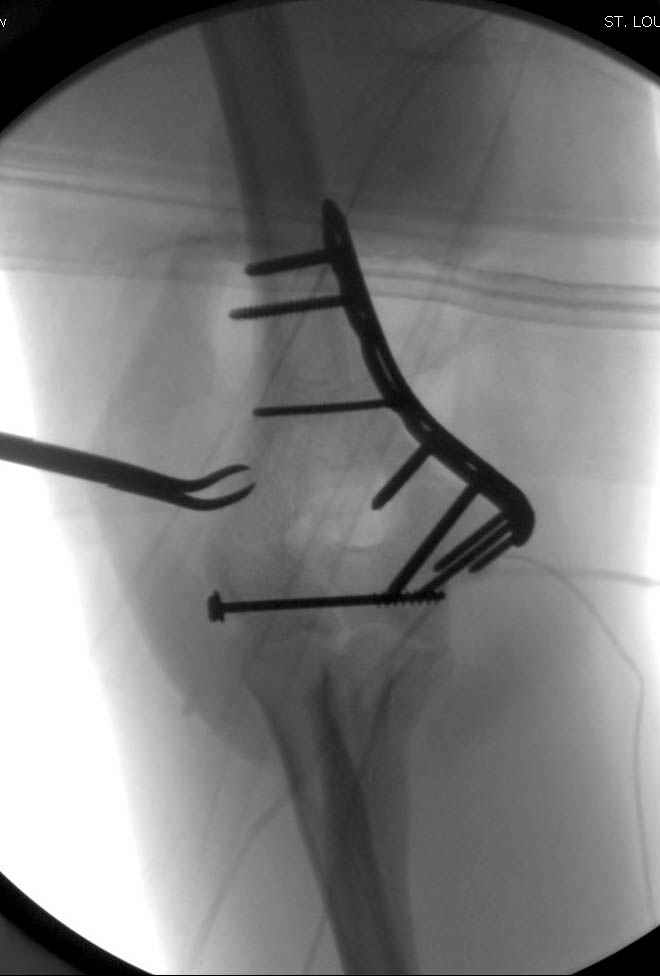

Примерный случай, только перелом был открытый, в задне-медиальной стороне рана около 2 см по характеру "изнутри кнаружи", неврологический статус со слабостью сгибания мизинца, также слабая абдукция и аддукция указательного пальца и сгибания в кисти.

Больному сделали обработку и наложили временный аппарат внешной фиксации плечо-предплечье.

На шестой день сделали открытую репозицию чрезлоктевым доступом двумя locking plate, локтевой нерв был ушибленным, после операции положительная динамика в Flexor Carpi Ulnaris. Фиксацию локтевого отростка произвели tension band technique с дополнительным шурупом.

Этапы операции на снимках....

Джолдас Кульджанов

Djoldas Kuldjanov, MD

Department of Orthopedic Surgery

St. Louis University Medical Center